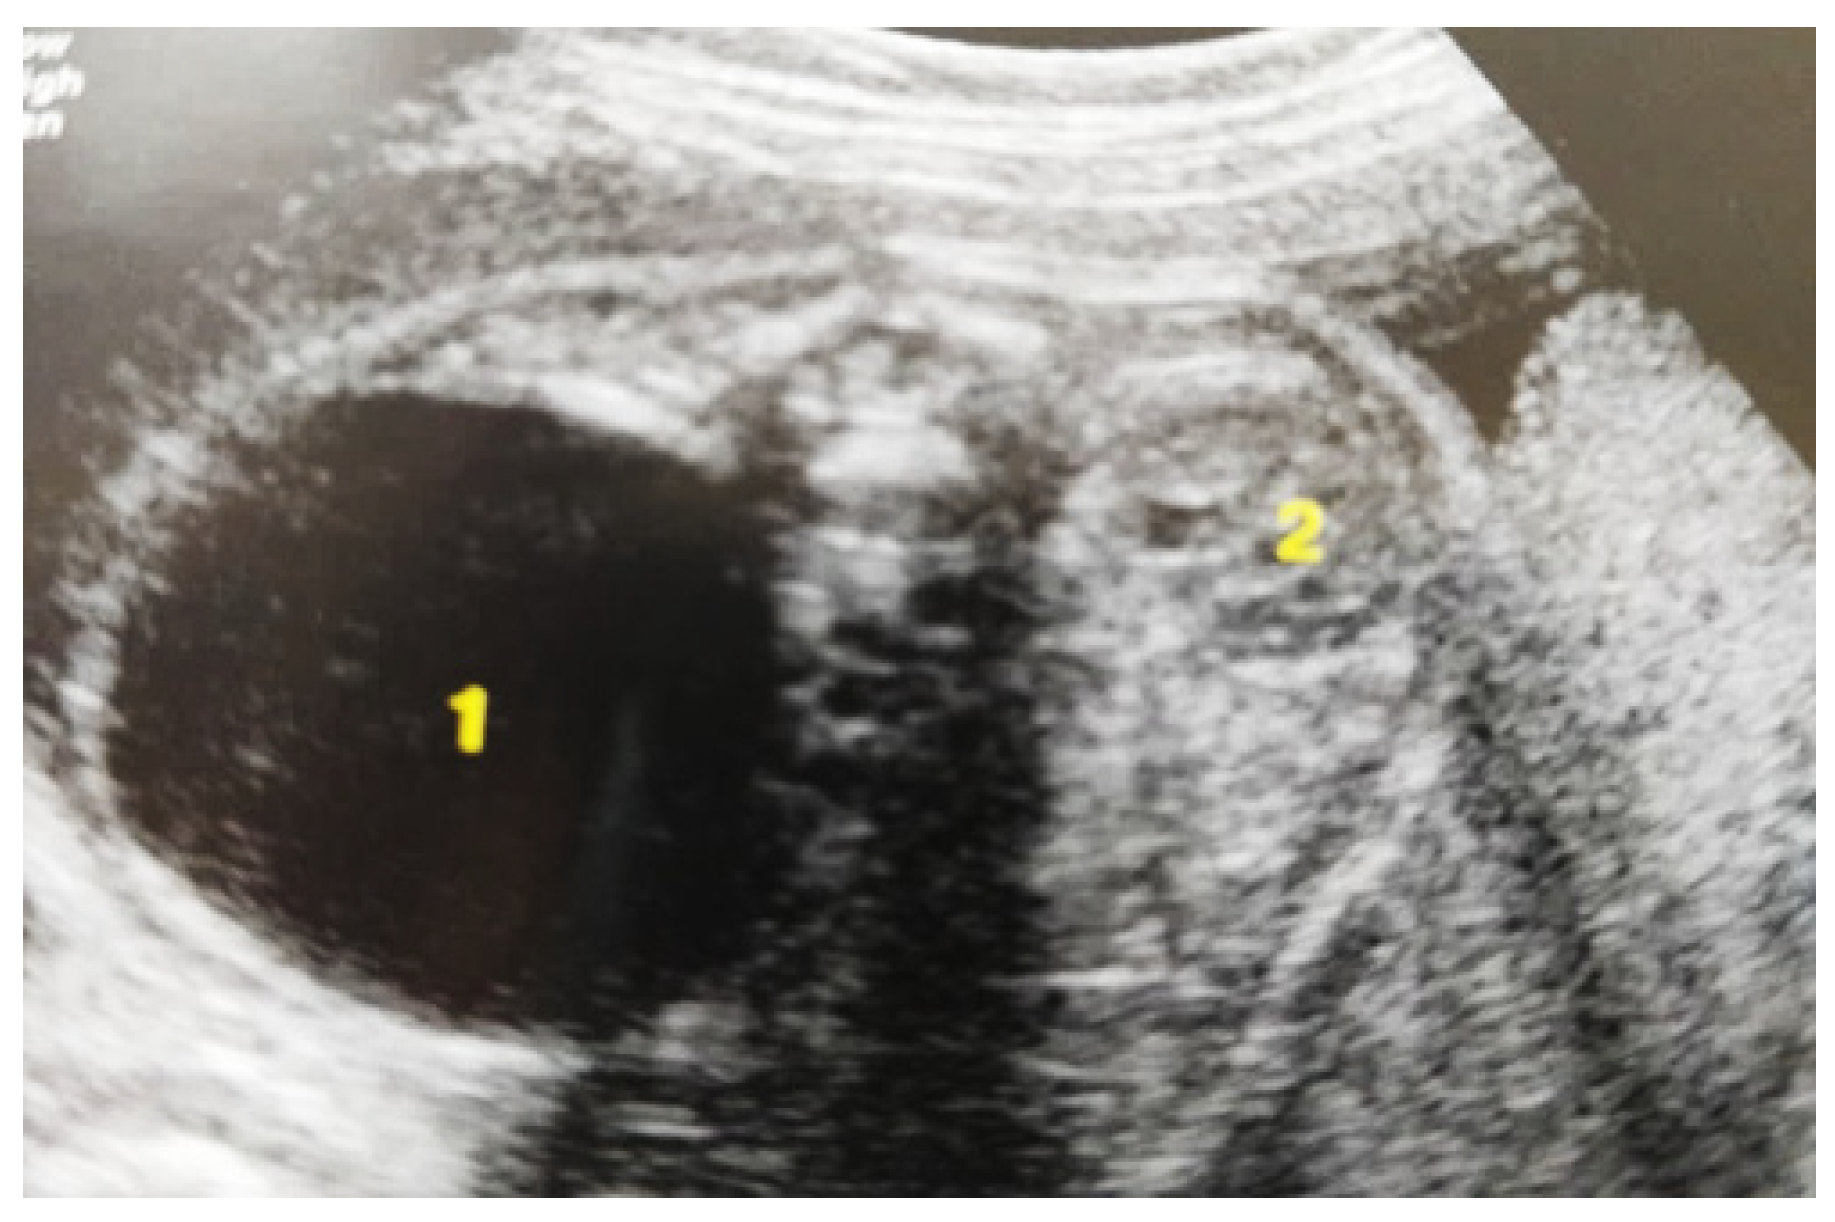

Our experience with congenital malformations of the urinary system refers to the following clinical case (Figure 2, Figure 3, Figure 4, Figure 5, Figure 6, Figure 7, Figure 8 and Figure 9). In the first case, during pregnancy, the 21-week ultrasound determined bilateral renal pyelectasia. The fetus had hydronephrosis on the right; at 31 weeks, it had bilateral hydrocalconephrosis; and at 32 weeks, bilateral pyelectasia. It suffered premature birth at 36 weeks, with complicated anomalies of the forces of contraction, prolonged birth, and birth weight of 2200 g. Postnatal ultrasonography was supplemented by intravenous urography, and bilateral hydronephrosis was determined. Hydrocalconephrosis on the left was discovered. The complete diagnosis was established: congenital renal malformation; bilateral pyelectasia; bilateral hydronephrosis; hydrocalconephrosis on the left; and severe reduced glomerular filtration rate (GFR), GFR > 2SD below mean.

Figure 3. Ultrasound at the 20th week of gestation. Hydronephrosis on the right. (1) Dilated pelvis on the right. (2) Uninjured renal parenchyma on the left.